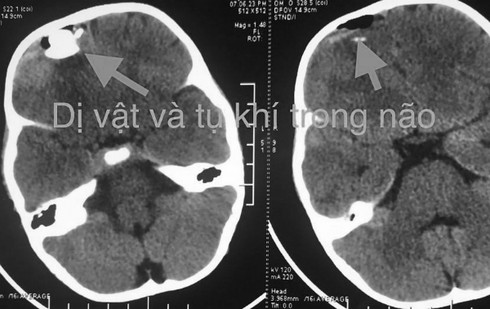

Ảnh chụp vị trí viên đạn nằm trong não của bệnh nhi. |

Trước tình huống khẩn, bệnh nhi lập tức được đưa vào phòng mổ. Các phẫu thuật viên ghi nhận viên bi gần như xuyên hoàn toàn qua lớp xương sọ, làm vỡ mảnh xương sọ đâm vào nhu mô não, làm rách màng cứng, chảy dịch não tủy và dập nhu mô não trán.

Theo các bác sĩ, may mắn viên đạn không xuyên quá sâu vào bên trong nhu mô não nên chưa gây tổn thương nghiêm trọng. Ngay sau khi viên đạn được lấy ra, sức khỏe của bé đã ổn định. Đến sáng 29/6, bé đã tỉnh táo và đang được theo dõi viêm màng não, động kinh.